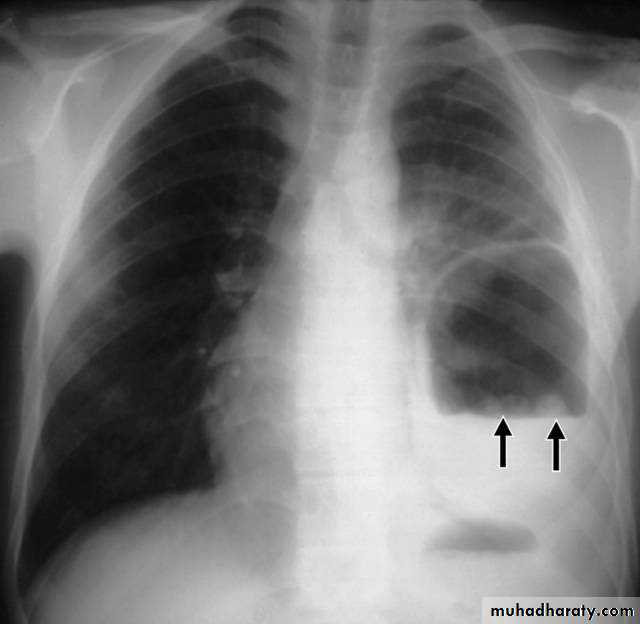

PneumothoraxX-ray pneumothorax

X-ray pneumothorax